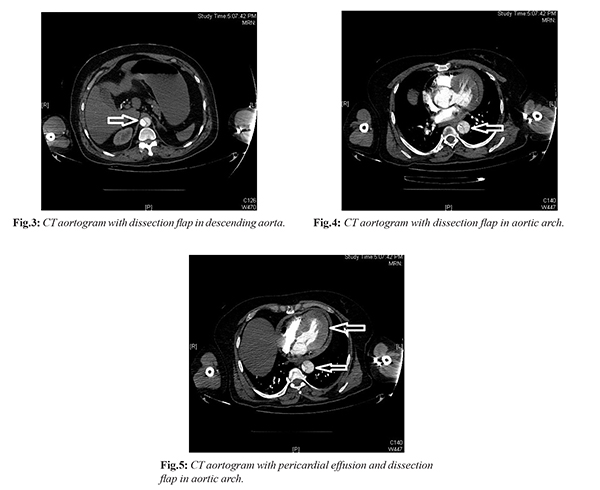

Electrocardiogram (ECG) was normal and patient underwent urgent bedside Trans-thoracic echocardiography (TTE) which revealed a dilated aortic root with flap in ascending aorta and arch with mild circumferential pericardial effusion [Fig.1,2]. He underwent elective rapid sequence intubation and was shifted for urgent CT aortogram which revealed acute aortic dissection (Standford Type A) with contained aortic rupture and pericardial effusion [Fig.3-5]. Urgent Cardiovascular and Thoracic Surgery (CTVS) consult was taken and patient shifted directly to the operation theater. Patient underwent Bentall’s procedure and was kept in the CTVS Intensive care unit post-operatively. Patient was kept on intravenous antibiotics, anticoagulants and other supportive treatment. Hospital stay was uneventful and patient was discharged in a stable condition after 10 days.